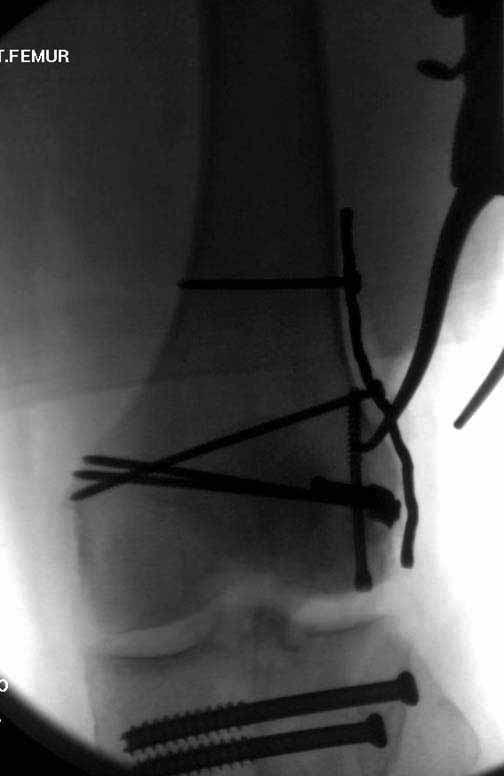

У больных как в этом случае, с вовлечением двух мыщелков правильно, что сделали вытяжение до операции. Здесь имеется флексионный компонент на другой стороне, и я бы рекомендовал операцию делать из двух доступов. Сперва фиксировать медиальную колонну custom made пластиной, обычно 1/3 тубулярной пластиной в 4.5 мм, потому что пока производители опаздывают с медиальной пластиной.

Пластину надо устанавливать на апексе перелома, иначе фрагмент начнет сползать. А на второй стороне, если имеется большой одиночный фрагмент тогда проблем не бывает, и их можно собрать компрессирующими винтами. Проблема наступает тогда когда многофрагментраность на латеральной стороне, где надо применить комбинированный метод, иногда несколькими пластинами. Или сменой позиции установки пластины, чтобы максимально прикрыть перелом и создать боковую поддержку.

Случаи могут быть разными и варианты фиксации могут быть различными. Это не эталон фиксации, и не каждый метод является "золотым стандартом". А “золотым” считается, когда внутрисуставной перелом отрепонирован на отлично и зафиксирован адекватно. Если возможно закрыто - хорошо, а так не надо искать только легкий закрытый путь, зная анатомию можно открывать, сколько надо!

Здесь пример медиальной пластины и латеральный комбинированный метод (у второго больного старый перелом тибиал плато, леченный где то и когда то)

В приложении пример недавней операции, C3, открытая репозиция, фиксация мыщелков спицами и винтами, ретроградный синтез большеберцовым гвоздем 10,5 мм диаметром, винты 5 мм.